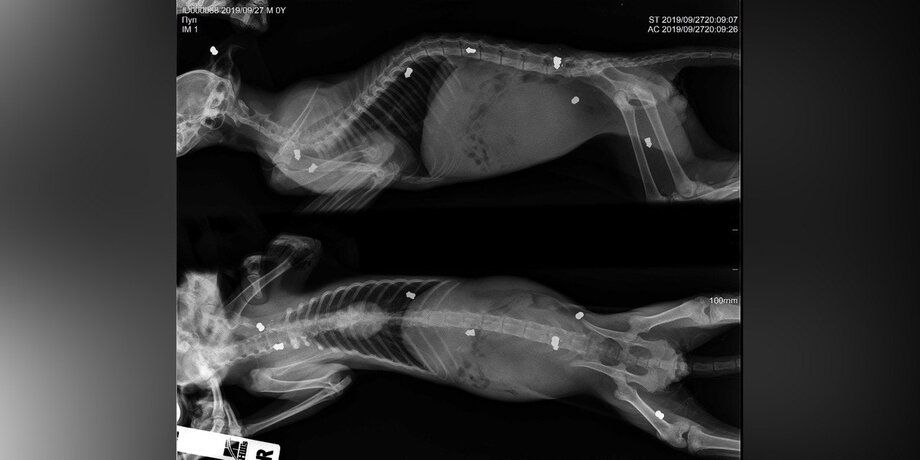

Мужчина сразу отнес котенка в клинику. Осмотр показал наличие девяти пневматических металлических пуль в его теле, две из которых попали прямо в позвоночник. Они уже буквально вросли в ткани животного. Из-за этого ветеринары пришли к выводу, что в него стреляли не на днях, а неделю или две назад.

Пули были "разбросаны" по телу: в задней левой лапе, в грудной клетке под кожей, благо не пробили ребра. Несмотря на то, что был поздний вечер пятницы, ветеринары остались после смены и оперировали в ночь. Сергей тоже присутствовал на операции, в клинике его давно уже знают и помогают.